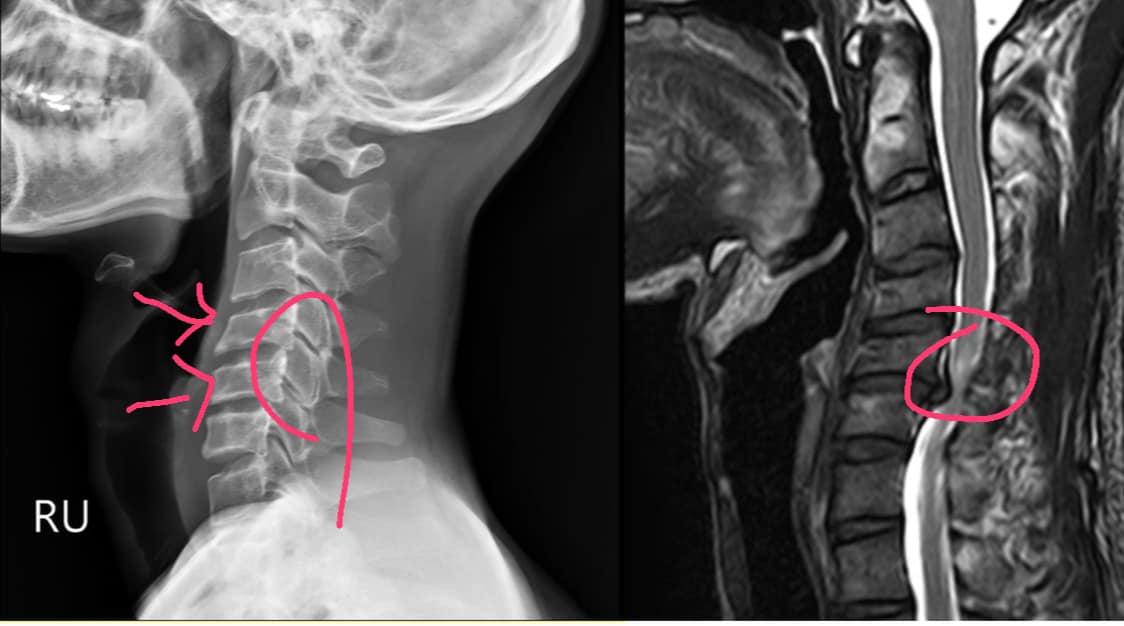

Cervical Spine Treatment Cases 見證影片 感謝宜蘭游小姐熱情見證 長達一年多時間痛到無法睡覺合併手麻 2020.05.29 #感謝台中戴先生熱情見證 #頸椎嚴重壓迫醫案 #原本手腳已經快沒力合併麻痛 #耐心治療... 2020.03.10 短短兩分鐘影片心酸血淚史 曾經腰痛連大腿小腿到無法睡覺 大醫院核磁共振檢查後證實椎... 2020.03.05 #腰椎明顯滑脫醫案 #感謝三重蔡先生熱情見證 #曾經大痛到無法工作跟無法睡覺 #脊椎整... 2020.03.07 腰椎滑脫第一度合併椎間孔狹窄第二度 原本痛到準備開刀,都拍完MRI,女兒帶 媽媽從雲... 2020.02.25 #頸椎神經根卡壓醫案 #三年的疼痛原本認真考慮頸椎開刀手術 #感謝張小姐熱情見證脊椎... 2020.02.28 #頸椎痛到無法睡覺怎麼回事 #神經根型頸椎病醫案 #感謝台北吳小姐熱情見證 #脊椎整合... 2020.02.18 #頸椎間盤突出痛到右手完全沒力 #神經根型頸椎病合併輕微脊髓壓迫 #原本考慮裝設人工... 2020.02.08 #跨國治療台灣醫療奇蹟 #遠從澳洲坐飛機回台專門接受治療 #台灣中醫脊椎整合微創療法... 2020.01.17 六次的治療讓患者完全脫離無法睡覺的惡夢,陳大哥說之前痛到晚上完全睡不著,他沒想到... 2020.01.10 #頸椎壓迫脊髓醫案 #原本認真考慮要去手術患者 #中醫微創療法真的逆轉勝 #前後核磁共... 2020.01.04 🆕聚焦「薦髂關節障礙」 #非典型下背痛醫案 #核磁共振有突出卻復健效果不好 #感謝新竹... 2019.11.21 有趣的醫案!感謝患者何先生願意熱情見 證分享,頸椎筋膜鬆動後,長期腰痛突然 改善,... 2019.11.20 ✅頸椎間盤突出痛到完全無法洗頭 💔核磁共振證實C4C5突出壓迫 😢上樓梯頭往後面抬就誘... 2019.11.13 #半夜腰痠痛原來是輕微的椎間盤突出 #感謝宜蘭患者熱情見證 #第一次治療就改善很明顯... 2019.05.30 ← 上一頁 36 37 38 39 40 下一頁 →